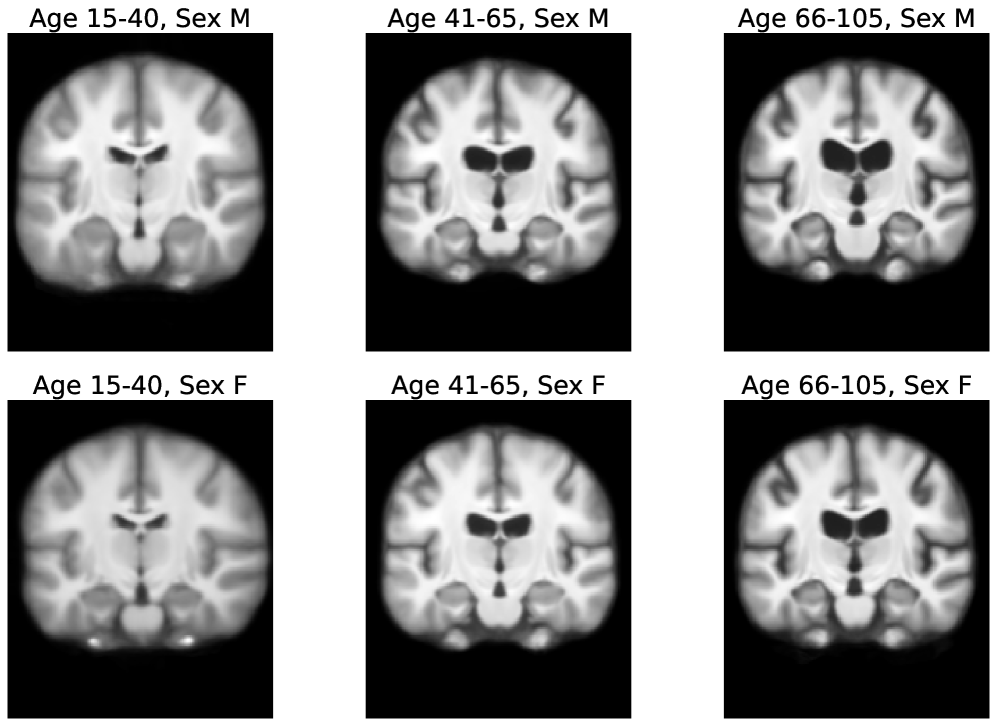

In this work, we present AtlasMorph, a learning strategy to generate conditional templates and corresponding anatomical label maps as a function of subject attributes. While we believe the strategy is general, in this paper we demonstrate it only on brain anatomy. Our method can leverage all the data available when constructing templates. There is no need to train a different network on a subset of the data for each combination of attributes. Figure 1 shows examples of templates, generated on demand by sampling our trained age-conditioned template function. Our framework can also adjust when label maps or subject attributes are missing.

Figures 5 and 6 show visualizations for templates produced by AtlasMorph and the AtlasMorph-Uncond variants. Supplemental Figure 15, and Figure 16 show templates optimized using ANTs. The Aladdin templates are shown in Supplementary Figure 17 and Figure 18. The learned AtlasMorph templates are significantly sharper than the average of the population, shown in Figure 4.

Conditional AtlasMorph captures variability across age that a single unconditional template cannot. For example, younger subjects have more grey matter, and ventricles get larger as subjects grow older. The intensities of the atlas involve contrast changes that are consistent with segmentation boundaries, capturing the alignment between the intensity templates and the segmentation templates. We include additional visualizations of templates conditioned on age, sex and disease (cognitively normal - mild cognitive impairment - Alzheimer’s disease) in the Supplemental Material, Figure 21.